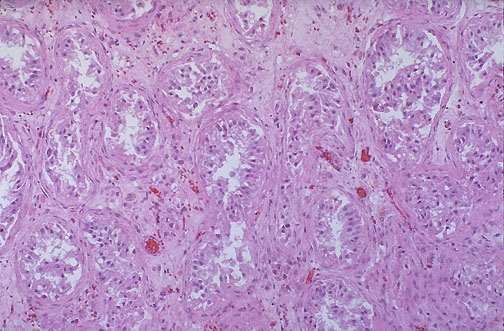

| Atrophic testis is demonstrated here. Note the marked loss of germ cells with remaining tall pink Sertoli cells, peritubular fibrosis, and interstitial fibrosis. If generalized, this is a cause for infertility. About half the time when infertility occurs in couples wanting children, the cause is a problem in the male genital system. |